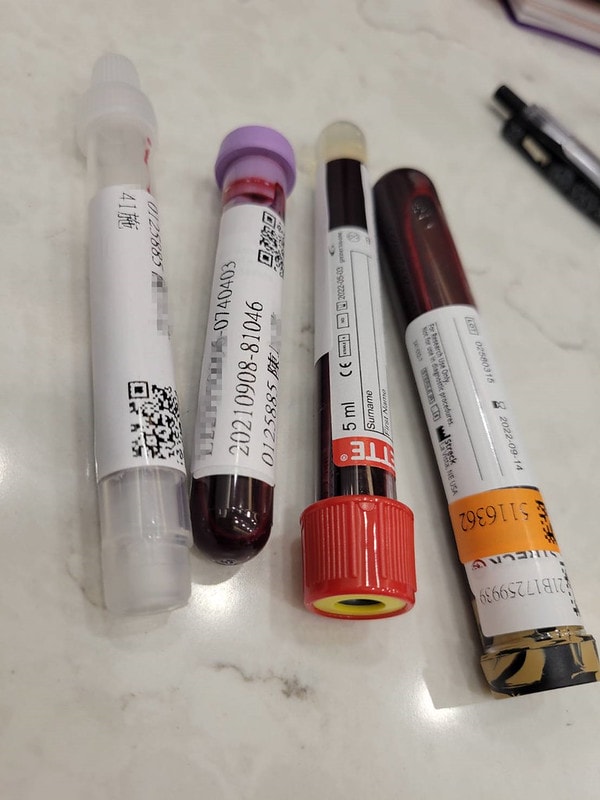

我做了NIPT+五合一+子癲前症總共大概三樣檢查

一開始最前面的話會有個健保給付的檢查報告

檢查的是:德國麻疹、AIDS、B型肝炎那些

只要是孕婦這個檢查是不另收費的

14周前一定要先做NIPT

我記得這天好像抽了五管血

非侵入性胎兒染色體檢測

我的診所有7項、20項、94項

費用從15000~38000都有

NIPT只要抽血就好了

所以我就是做了以上說的NIPT+五合一+子癲前症這三樣檢查